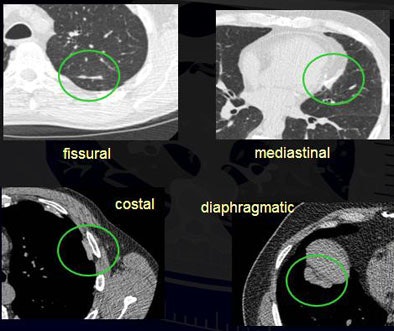

The results showed that 308 (73%) patients had pleural plaques. At least 83% of the plaques had at least some calcification, ranging from "tiny spots" at CT to complete calcification in 11%. Most involved the costal (more than 97% of plaques) and diaphragmatic (more than 88% of plaques) pleura.

| Researchers found that more than 86% of pleural plaques were completely flat and 91% were symmetrical. Eleven percent of patients had diffuse pleural thickening (top). Plaques that were asymmetrical in shape and mass-like were considered suspicious for malignancy (above). Plaques were detected in the lung fissures, mediastinum, diaphragm, and costal regions (below). All images courtesy of Dr. Heidi Roberts. |